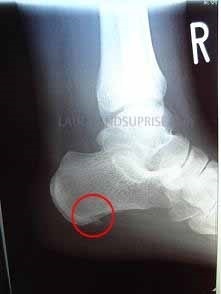

レントゲンを早速撮ってこられ、整形外科では踵骨骨棘(しょうこつこつきょく)と足底腱膜炎(そくていけんまくえん)でしょうという診断があったとのことでした。 下の写真は当患者様からお預かりしたレントゲン写真です。踵骨に棘ができているのがはっきり分かります。

*レントゲンの掲載については患者様の了解を得ております。